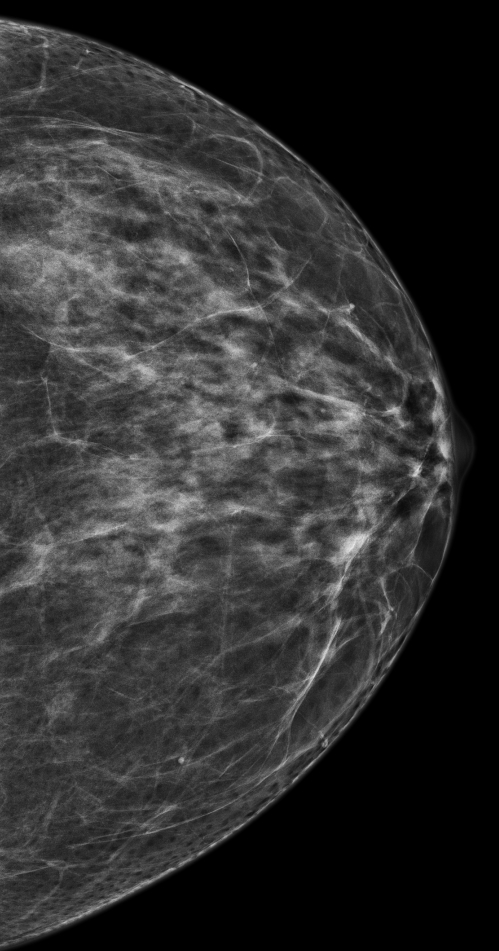

유방촬영기(Mammography System)는 저선량 X-ray를 이용해 유방 내부 조직을 촬영하는 영상진단 장비입니다. 병변, 석회화, 결절 등 유방 내 이상 구조를 선명하게 포착할 수 있어 유방암 조기 발견</strong에 매우 효과적입니다.

- 디지털 유방촬영기(Digital Mammography, DM): 디지털 감지 센서를 사용해 이미지 데이터를 실시간 저장하고 판독.

- 디지털 톰오신시스(DBT, 3D Mammography): 다양한 각도에서 촬영하여 유방의 3차원 구조를 구현. 조직 겹침 최소화로 진단 정확도 향상.

- 고해상도 이미지: 미세 석회화, 결절 등을 더 선명하게 확인 가능